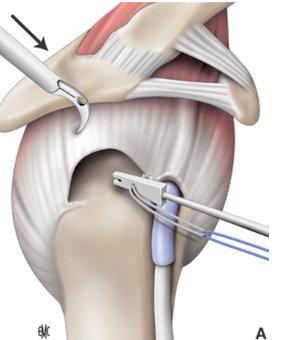

¿QUÉ ES LA PLASTIA DEL MANGUITO ROTADOR?

La plastia del manguito rotador, también conocida como reparación del manguito rotador, es una cirugía que tiene como objetivo reparar los tendones desgarrados en el hombro.

¿EN QUÉ CONSISTE LA CIRUGÍA?

El procedimiento consiste en volver a unir los tendones desgarrados al hueso utilizando suturas o anclajes especiales. Esta cirugía puede realizarse de dos maneras:

Reparación artroscópica

Se utiliza una cámara pequeña (artroscopio) para visualizar y reparar los tejidos dentro de la articulación del hombro a través de pequeñas incisiones.

Reparación abierta

Se realiza a través de una incisión más amplia en el hombro, permitiendo una exposición directa de los tendones lesionados.